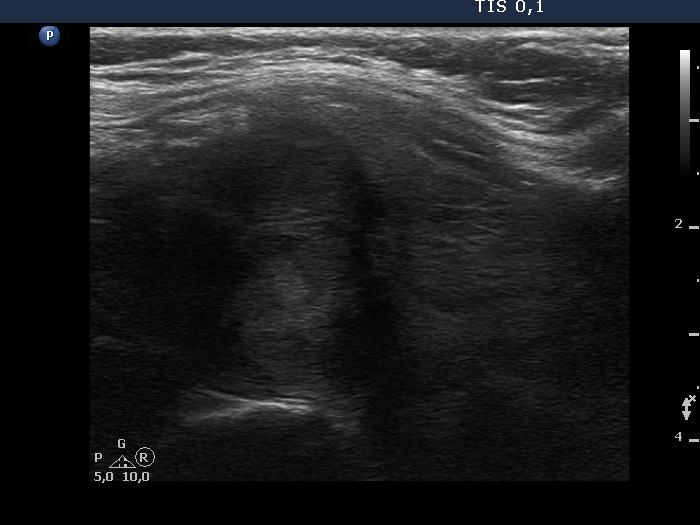

Follow-up examination six years after the first visit (ultrasonographic picture 9)

Left lobe, another longitudinal scan.